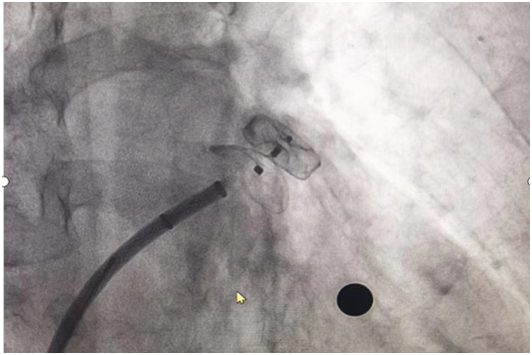

左心耳封堵:

先天性心脏病介入封堵: